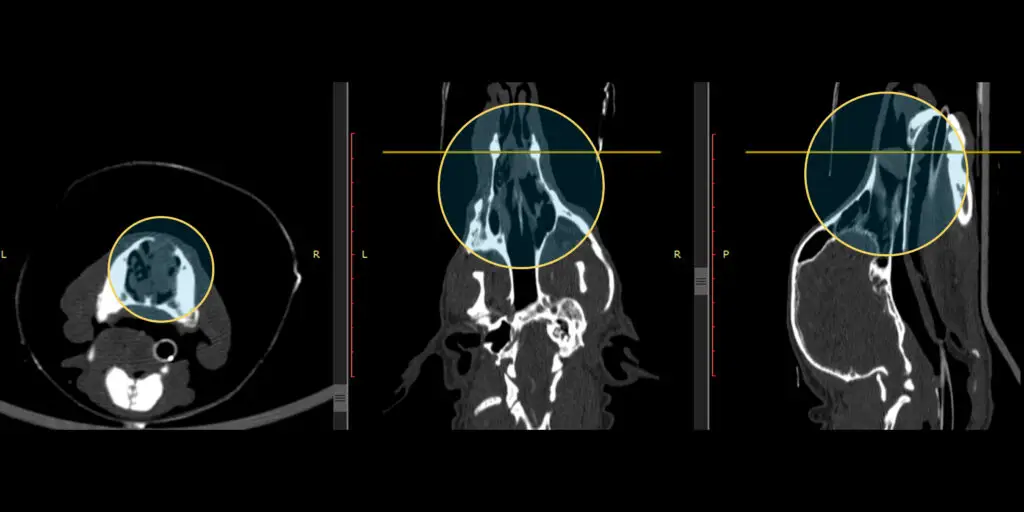

• Especie / Raza / Edad: Canino, Shiba Inu, Macho, 8 años.

• Localización anatómica: Cavidad nasal derecha, estadio Adams II.

• Histología tumoral: Sarcoma nasal.

• Historia clínica: El paciente inició con sangrado nasal. Se realizó endoscopía, con resultado de sarcoma nasal. La tomografía computarizada (TC) visualizó el compromiso de la cavidad nasal derecha y seno frontal.

• Protocolo de Tratamiento: Se prescribió una dosis total de 36 Gy, fraccionada en 6 sesiones de 6 Gy, con una frecuencia de 2 veces por semana .

Resultados: Al año de tratamiento se mantiene libre de signos respiratorios, llevando una vida normal.